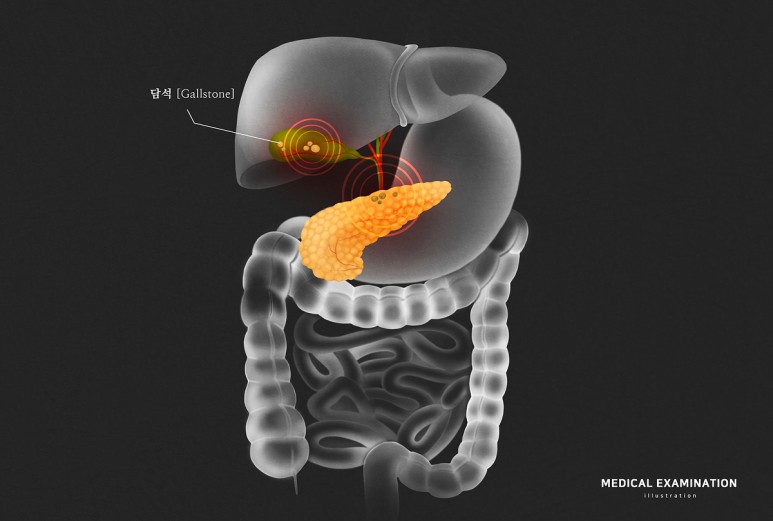

담석 증원의 소화불량이 계속되고 있는 경우는

다이어트를 장기간 하거나 이와 반대로 맵고 짜고 기름지고 자극적인 음식을 과식하면 소화 기능이 약해져 위장 관련 질환에 쉽게 노출될 수 있습니다.또 담석증 같은 질환이 발생하는 경우도 흔히 볼 수 있는데 이름만 들어보면 생소한 질환이지만 우리나라 노년층 환자에서 발생 비율이 높은 편이라고 합니다.소화불량에 더해 복통 등의 증상이 지속되고 있는 경우에는 담석증을 의심해볼 수도 있습니다.그럼 오늘은 많은 분들께 생소한 담석증의 원인과 증상, 치료 방법에 대해 알아보는 시간을 갖도록 하겠습니다.

담석증은 우리가 흔히 담낭이라 불리는 담낭에 저장된 액체가 돌조각처럼 딱딱하게 굳어져 형성되는 것을 말합니다.담낭은 작은 주머니 모양의 구조로 복부의 오른쪽 상단, 간 아래에 위치하고 있습니다.담즙이라 불리는 액체는 지방의 소화를 돕기 위해 필요한데, 간에서 생성된 후 담낭 속에 저장돼 우리가 밥을 먹을 때 담낭이 수축되면서 총담간이라 불리는 관에 담즙을 눌러 십이지장에 담즙이 배출돼 음식물의 소화를 돕게 됩니다.

담석은 크게 콜레스테롤성 담석과 색소성 담석으로 나뉘는데, 각각의 담석의 증원인은 다르다고 할 수 있습니다.콜레스테롤성 담석은 담즙이 함유된 성분 중 콜레스테롤의 양이 증가하여 발생하는 것을 말하며 각종 감염이나 만성 간질환, 위절제수술 등으로 인한 췌장관계 변화에 의해서도 발생할 수 있어 보다 각별한 주의와 관리가 필요합니다.색소성 담석은 주로 세균 감염에 의해 발생하는데, 간경변이 있는 환자나 담도 계통의 염증이 있는 환자, 겸상적 혈구성 빈혈과 같은 유전적 혈액질환이 있는 환자에게서 쉽게 발생합니다.

담석증의 일반적인 증상으로는 복부 팽만감이나 트림, 가스, 소화불량 등의 흔히 우리가 느끼는 증상이 있으며 아무런 증상이 없으며 이와 반대로 심할 때에는 심한 복부 통증이 발생하기도 합니다.가장 특징적인 증상은 담석산통이라고 해서 통증이 명치부터 시작하여 오른쪽 상복부에 이르기까지 심한 증상이 발생하는 것을 말하는데 자극적인 식후 증상이 발생하는 경우가 있으며 만약 아래와 같은 증상이 있다면 담석산통을 의심해 보는 것이 좋습니다.- 등쪽 어깨 사이에 발생하는 통증 – 오른쪽 어깨 아래까지의 통증 – 오심과 구토

담석증의 원인은 다양하기 때문에 증상이 나타났을 때 구체적인 원인과 양상을 파악하고 치료를 진행해야 합니다.적절한 치료를 하지 않을 경우 패혈증으로 이어져 사망에까지 이를 수 있으므로 조기 발견과 치료가 중요합니다.증상이 심하지 않으면 담석이나 통증이 있는 부위에 열을 가하는 등의 치료를 할 수 있으며 수술이 필요한 경우 개복술이나 복강경 하담낭 절제술 등의 방법을 생각할 수 있습니다.

담석증을 예방하기 위해서는 먼저 규칙적인 식사 습관을 길러야 합니다.고지방, 고칼로리의 자극적인 음식을 과다 섭취하는 것을 삼가고 섬유소류, 비타민, 미네랄, 채소류를 골고루 섭취하는 것이 도움이 됩니다.자주 나타나는 소화불량이나 복통, 가볍게 넘기지 말고 불편이 점점 심해지면 의료기관에 내원하여 진단을 받아보시기 바랍니다.